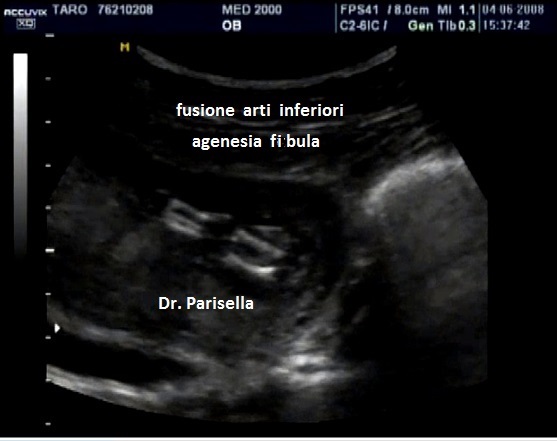

aplasia fibula

La displasia boomerang รจ una sindrome estremamente rara caratterizzata da nanismo micromelico con arti ricurvi e rigidi, difetti di ossificazione, aplasia della fibula, aplasia del radio, facies caratteristica con radice del naso ampia ed ipoplasia delle narici e del setto nasale.

Il termine boomerang si riferisce alla particolare forma delle ossa lunghe delle gambe.